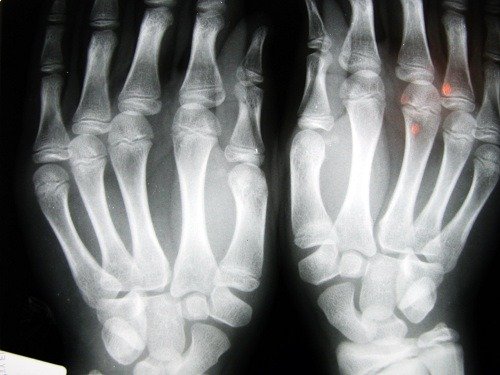

骨質疏鬆症是一種導致骨密度降低的骨骼疾病,此疾病的特徵在於多孔的骨頭。藉由增加骨內細胞的尺寸,它們變脆弱易碎並且更容易斷裂。

這種疾病是沉默的,因為它經常沒被注意到,直到它已經對骨骼造成損害。

骨折經常發生在手腕上,也會發生在髖部的椎骨中。這是最嚴重的骨折,因為它涉及到立即性的外科手術並且對患者健康有嚴重後果。